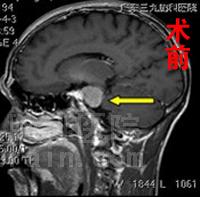

入院完善相关检查,头颅磁共振检查见左侧桥小脑区占位,考虑脑膜瘤可能性大,结合其他检查很快为其制定了手术方案,手术由微侵袭神经外科吴杰主任主刀,术程顺利,术中大部分切除肿瘤。术后病理回报:符合脑膜瘤。患者刘先生恢复情况良好,术前头晕、头痛等症状消失。